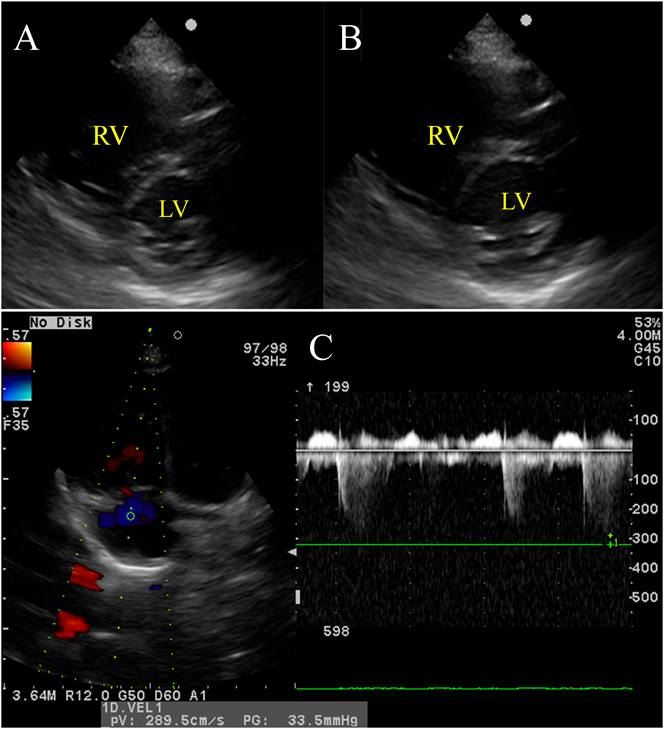

Chest radiography showed no abnormalities in the lung field and no cardiac enlargement. The main pulmonary artery was slightly enlarged (Fig. 1). Electrocardiography (ECG) showed a sinus rhythm with right axis deviation (Fig. 2). Echocardiography revealed enlargement of the right ventricle (RV) and right atrium (RA) and bulging of the interventricular septum to the left ventricle (LV). Tricuspid regurgitation (TR) was moderate, with a peak TR jet velocity of 4.29 m/s (Fig. 3). RV pressure was estimated to be 73 mmHg plus RA pressure; accordingly, severe PAH was suspected. Contrast echocardiography was performed to differentiate diseases causing hypoxemia. Microbubbles were stagnant in the RA and RV, with RV function markedly deteriorated, and did not enter into the left heart. A sildenafil (1 mg/kg) administration test was carried out through a nasogastric tube under oxygen administration using a high flow nasal cannula. One hour later, echocardiography showed that the abnormal arrangement of the interventricular septum had become normally round, that TR had improved to mild, and that the peak TR jet velocity had attenuated to 2.89 m/s (Fig. 4). Tachycardia and tachypnea disappeared, and blood pressure came up. Based on his dietary history, thiamine (30 mg) was injected intravenously followed by oral thiamine (25 mg/day) continued for possible cardiovascular beriberi due to vitamin B1 deficiency. Since idiopathic PAH could not be ruled out entirely, tadalafil (1 mg/kg/day) was started from the day of admission. TR eventually disappeared on echocardiography on the same day. The RV and the RA gradually became smaller.

Fig. 4 (A) One hour after administration of sildenafil, echocardiography (short axis view) at end-systole showed that the interventricular septum was almost round. (B) At end-diastole, the left ventricular dimension appeared greater comparing to that before sildenafil treatment. (C) A peak tricuspid regurgitant velocity came down to 2.89 m/s